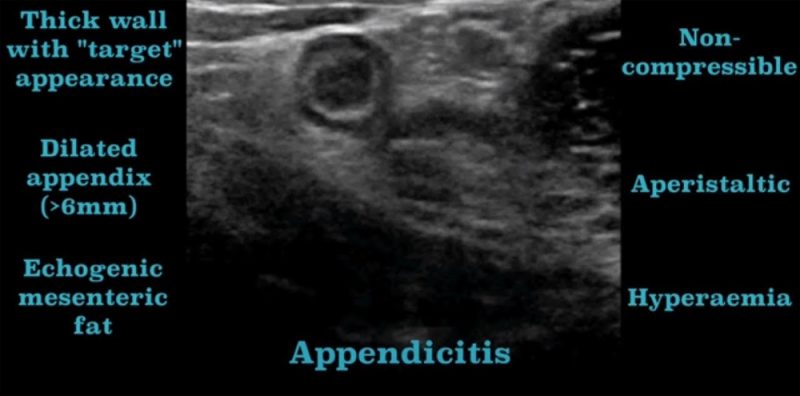

Една од поновите примени на Ехо -ултрасонографијата е во дијагностицирање на слепо црево -акутен апендисцитис при постоење на тубуларна формација со дијаметар над 6 мм некомпресибилна при притисок со сондата и задебелени ѕидови во областа на илеоцекалната регија над .m.psoas понекогаш со присуство на слободна анехогена течност во околина што укажува на перфорација со иритација на перитонеум.